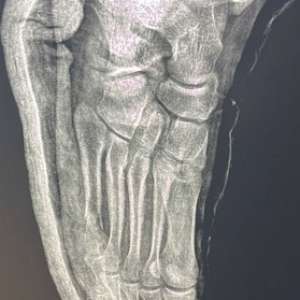

Пациент обратился с жалобой:перелом(первое фото)